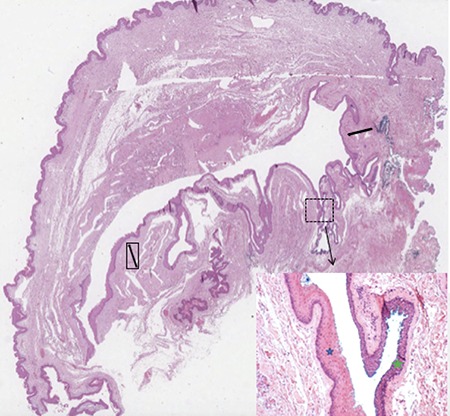

Figure 3.

Microscopic overview of the surgical specimen showing a large hybrid epidermal inclusion cyst (black arrows) lined by squamous epithelium (blue star) with areas of transitional epithelium (green star; haematoxylin and eosin stains).